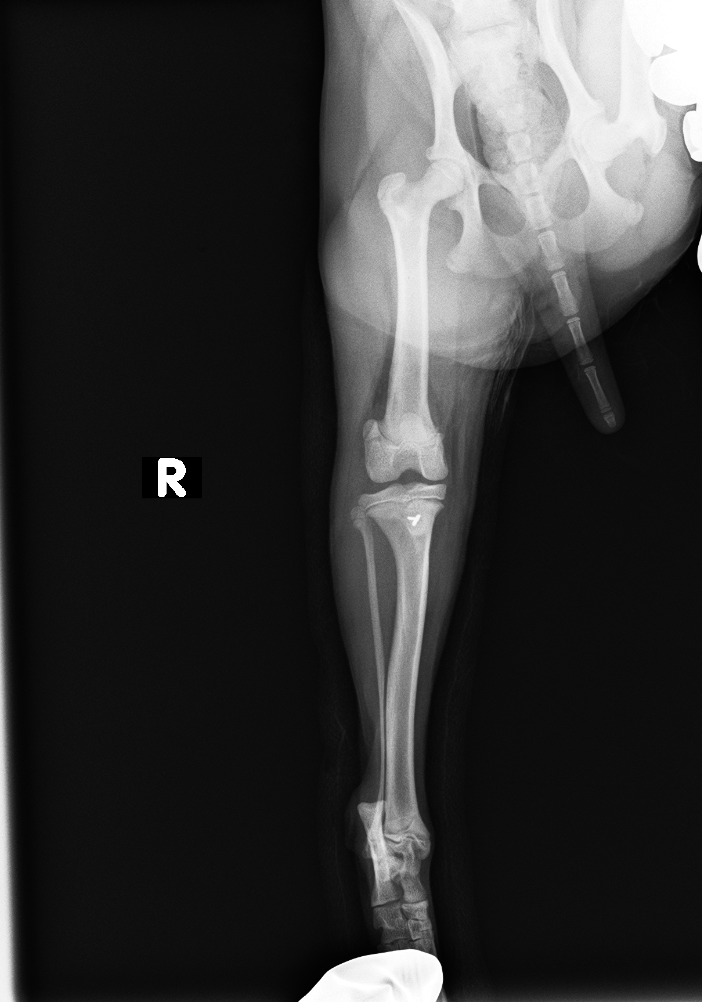

レントゲン検査より、脛骨粗面成長板の剥離

before